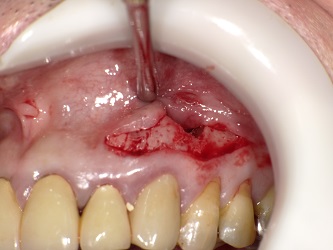

写真が悪いですが

歯根端切除の様子です。

歯茎を開き

病巣を掻把し 根の先端を骨のレベルでCUTし逆根充

骨に置換される薬を置き 歯茎を戻し終了です。